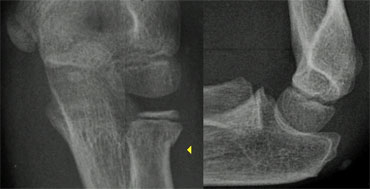

The diagnosis of a lateral condyle fracture can be challenging.

Fracture lines are sometimes barely visible (figure).

Remembering the fact that the lateral condyle fracture is the second most common elbow-fracture in children and because you know where to look for will help you

Lateral condyle fracture. On the x-ray only a small metaphyseal fragment is visible. The detatched fragment however is larger than it appears on the radiograph. The fracture extents into the lateral ridge of the trochlea. Elbow is probably unstable. Lateral condyle fracture. On the x-ray only a small metaphyseal fragment is visible. The detatched fragment however is larger than it appears on the radiograph. The fracture extents into the lateral ridge of the trochlea. Elbow is probably unstable.

Lateral Condyle fractures (4) .

Since most of the structures involved are cartilageneous, it is very difficult to know the exact extent of the fracture.